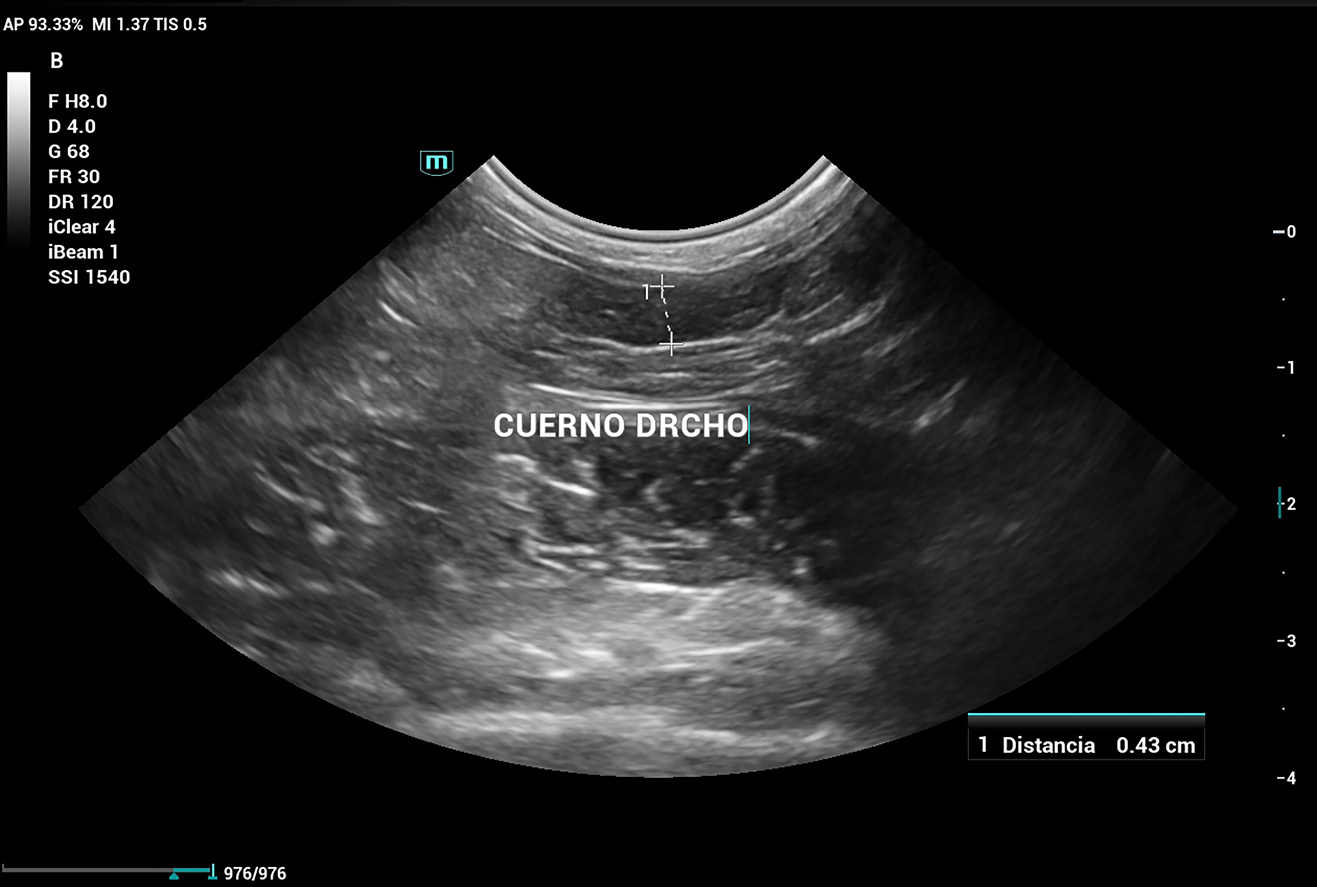

Se realiza ecografía abdominal, que evidencia que aún cuenta con cuernos uterinos (imagen 6), lo que confirma la ovariectomía (no ovariohisterectomía). Por este motivo, se decide enviar una muestra de plasma sanguíneo a un laboratorio externo para evaluar los niveles de 17β-estradiol, dado que en ecografía no se logra distinguir con claridad un remanente ovárico.